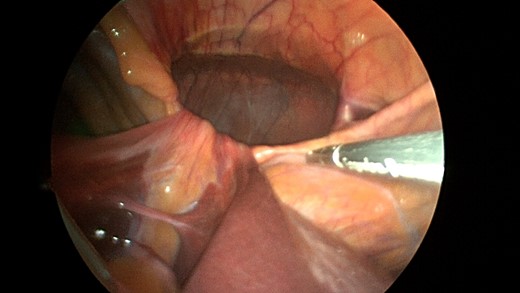

Patient underwent a laparoscopic approach in lithotomy positioning with the primary surgeon working between the legs. Three working ports were used, a 12 mm port at the umbilicus and two 5 mm ports; one in the LUQ and one in the RUQ. Upon initial laparoscopy multiple loops of small bowel were progressively reduced out of the hernia sac which also included the ascending colon and part of the transverse colon (Figs 3 and 4). All the small bowel and the colon appeared viable. The redundant parietal peritoneal hernia sac was excised out of the right inferior hemithorax utilizing a LigaSure (Covidien) (Fig. 5). The falciform ligament was also taken down all the way to the diaphragm. The defect in the diaphragm measured to be approximately 9 cm by 4 cm. A section of Pariatex composite mesh was then trimmed to 2 cm in width by 9 cm in length. Three stay sutures of 0 Ethibond were placed laterally and in the middle of the mesh. This was placed into the peritoneal cavity after soaking it in vancomycin with local anesthetic. The sutures were then percutaneously brought through the diaphragm edge that was unattached to the anterior abdominal wall and then subsequently through the anterior abdominal wall. These were then tied thereby re-approximating the unattached edge of the diaphragm to the anterior abdominal wall near the xiphoid (Fig. 6). Additional 0 Ethibond sutures were placed in between these initial ones percutaneously with a suture passer.

Laparoscopic view of the retroxyphoid defect in the diaphragm demonstrating multiple loops of small bowel and colon.

Closer view of the retroxyphoid defect demonstrating its large size with the edge of the diaphragm unattached to the undersurface of the abdominal wall.